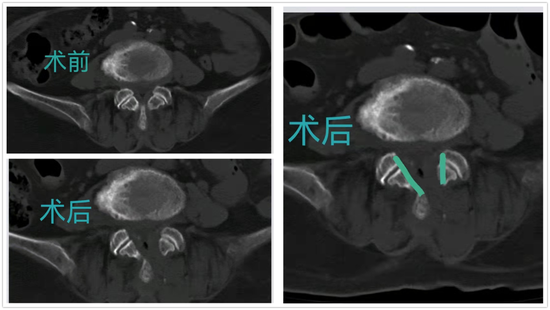

随着微创技术的快速发展,以脊柱内镜为代表的脊柱微创技术,已经在临床上广泛应用,并取得了满意的临床疗效。脊柱内镜技术与传统开放手术相比,它是借助天然解剖间隙建立微创工作通道,去除突出的椎间盘,扩大椎管,以解除神经压迫;对椎旁肌肉损伤较小,且能够最大程度地保留完整的脊柱结构,维持了术后脊柱的稳定性,具有创伤小、出血少、恢复快、并发症少、疗效确切等优点,是近年来大家关注和研究的热点。

△术前术后CT对比图